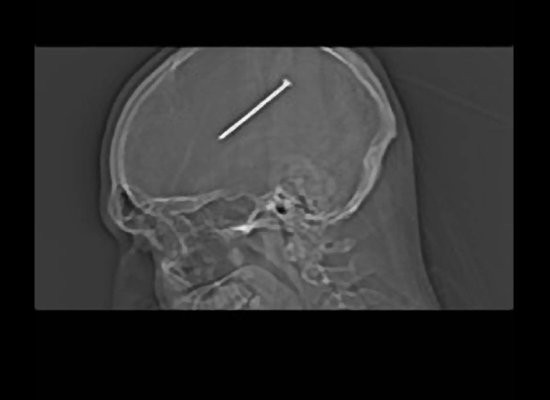

I-a blocat pana si pe medici.Ce au gasit in creierul unui barbat. Pacientul nici macar nu stia.VIDEO

A stat o zi intreaga cu un cui de aproape 8 cm in cap si n-a simtit nimic. Un american din Illinois s-a impuscat ...